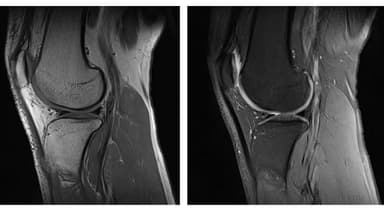

– Các bệnh liên quan về xương khớp: Trong các trường hợp gãy xương, phù tủy xương, nghi ngờ các tổn thương ở khớp vai, khớp háng, khớp khuỷu tay, cổ tay, cổ chân,…